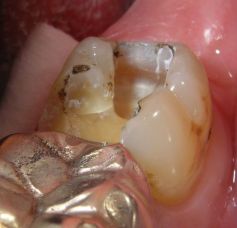

Schmerzhafter Haarriß, mit Amalgam beschwerdefrei

Gleicher Zahn (37). Zuverlässige Therapie einer schmerzhaften Infraktur, d. h. eines unvollständigen Zahnbruches, mit Amalgam, die mit Composite vermutlich nicht funktioniert hätte.